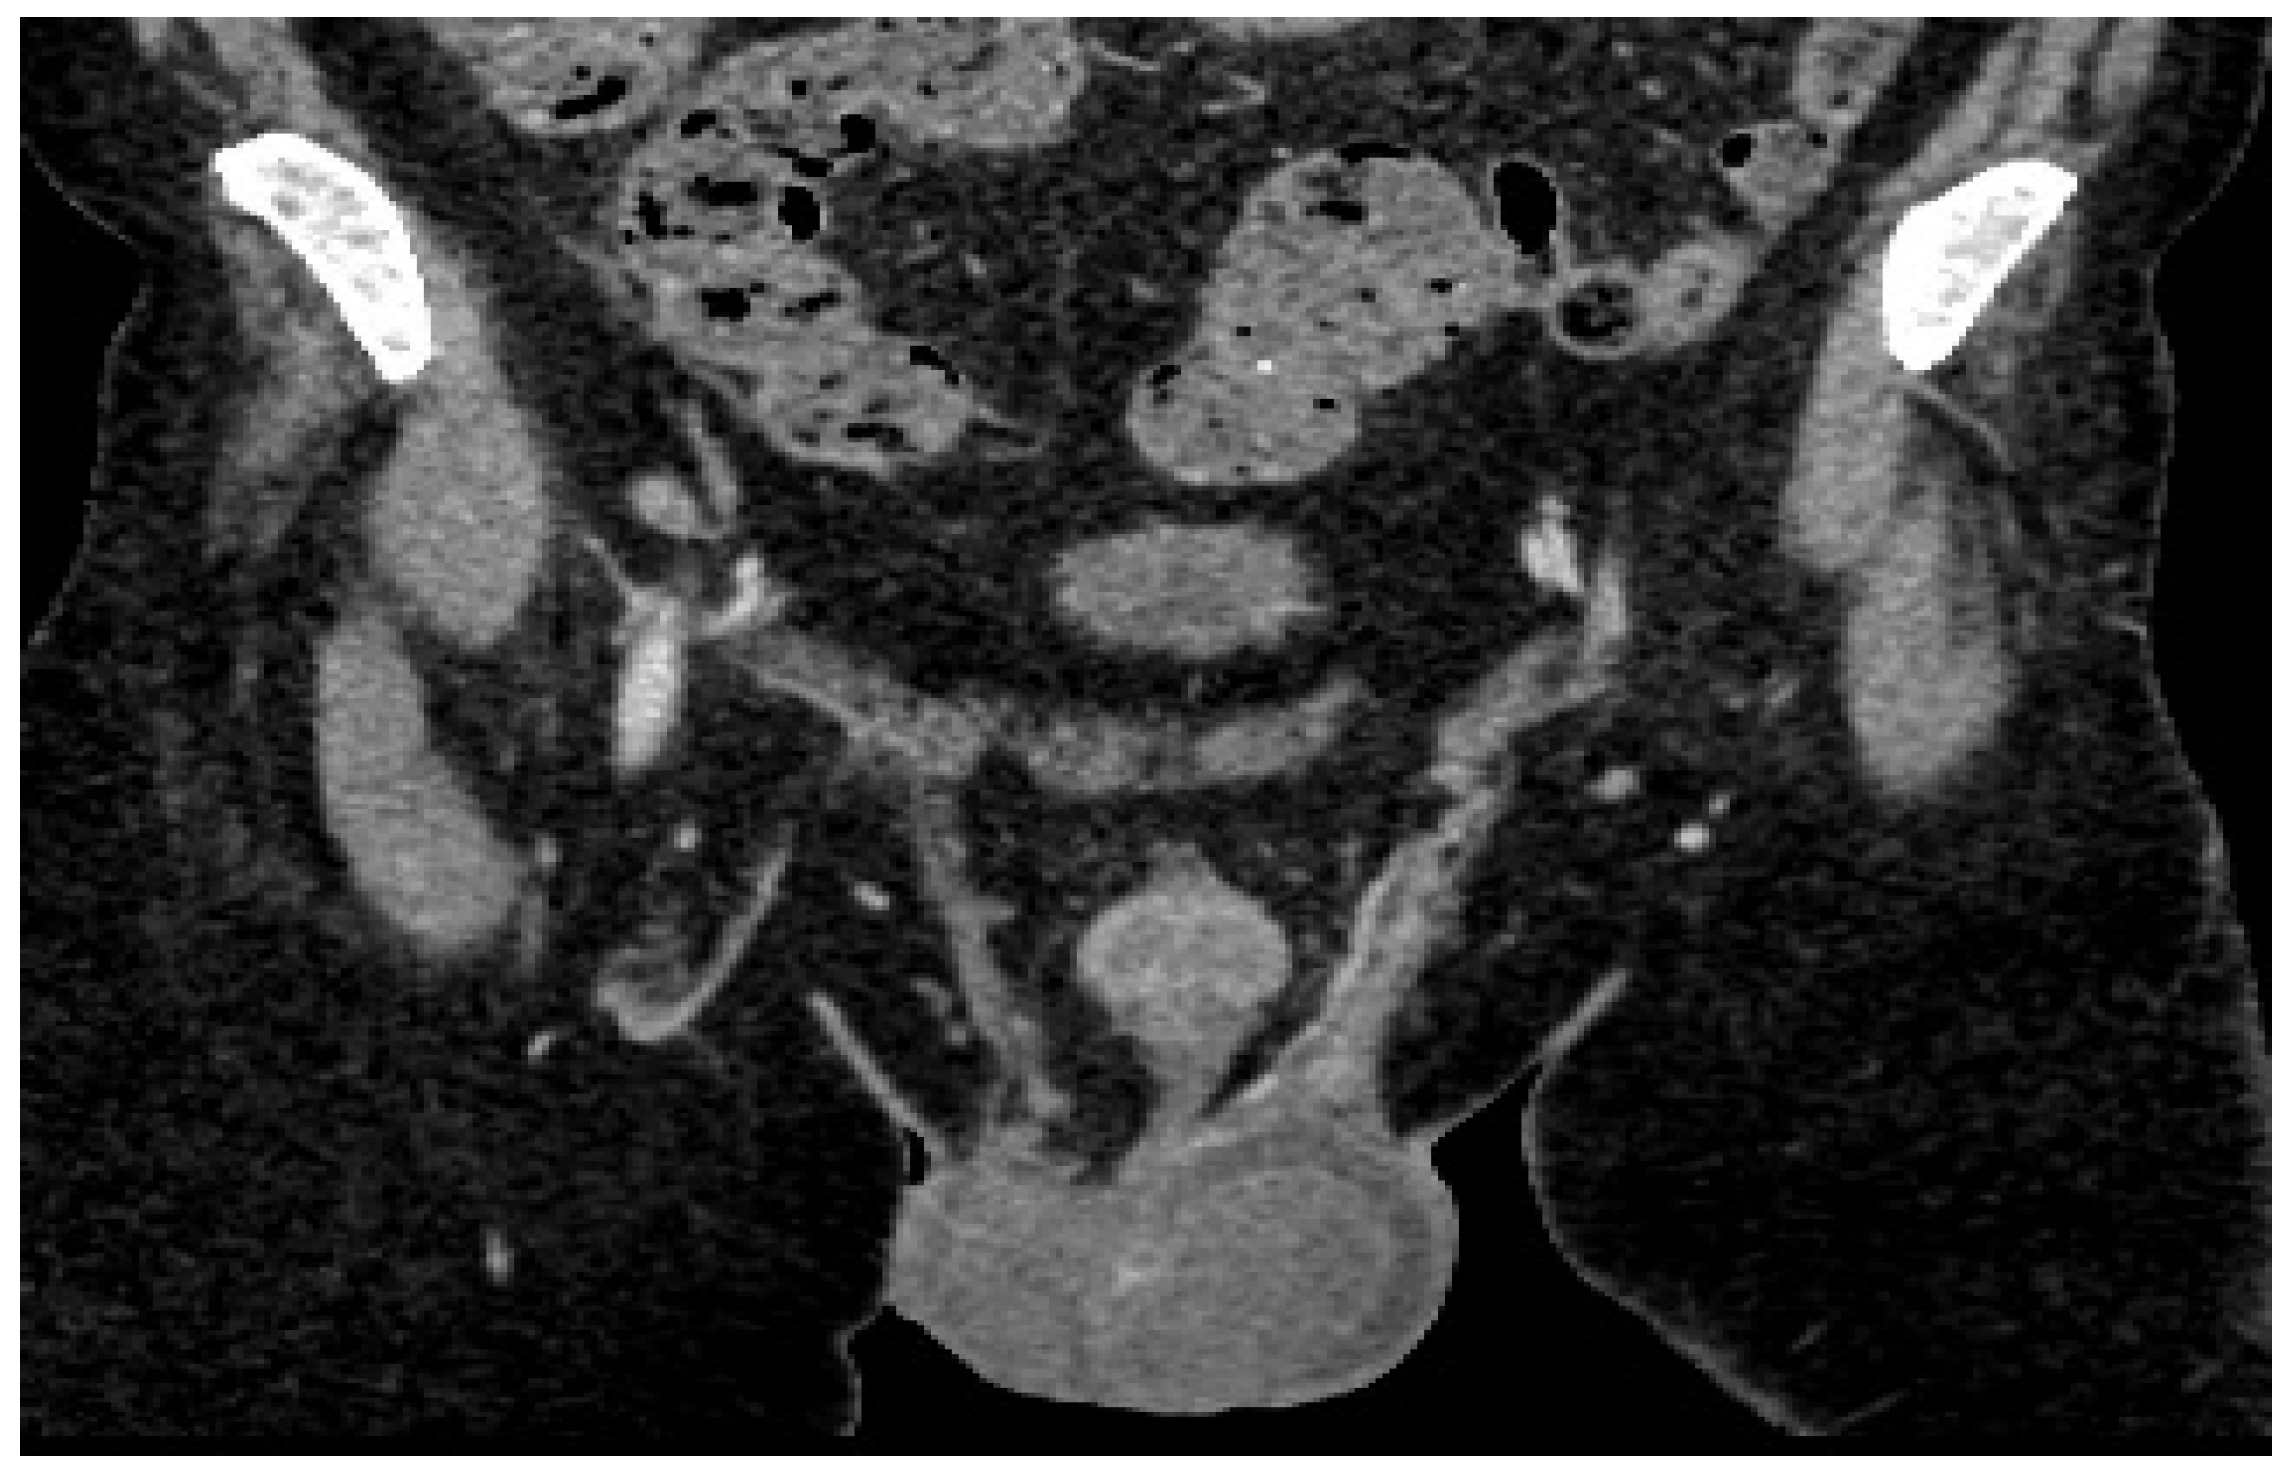

CT examination reveals the left testicle with a regressed dimensional appearance, with current dimensions of 50/40/40 mm vs. 100/60/60 mm and reduced iodophilia compared to the previous examination (Figure 4). Adenopathy along the left testicular vein appeared reduced in size with a maximum diameter of up to 20 mm.

Figure 4.

Follow-up post-chemotherapy CT of abdomen and pelvis shows left testicle and adenopathy reduced in size.